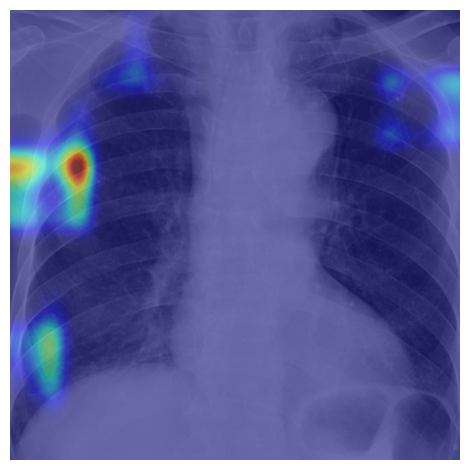

Refer to caption

(a) Healthy(1)

(b) NODE21

(c) Healthy(2)

(d) VinDr-CXR

Figure 5: Grad-CAM-based saliency maps illustrating model interpretability across datasets. Top row: Examples from NODE21 showing baseline (a) and curriculum-trained (b) models. Bottom row: Examples from VinDr-CXR demonstrating consistent attention patterns (c, d).

Grad-CAM visualizations showed that curriculum-trained models consistently focused on anatomically meaningful lung regions near nodules (Figure 5b), while baseline models activated broader, clinically irrelevant regions (Figure 5a). Similar attention patterns were observed across NODE21 and VinDr-CXR examples (Figure 5c,d), supporting interpretability and robustness.